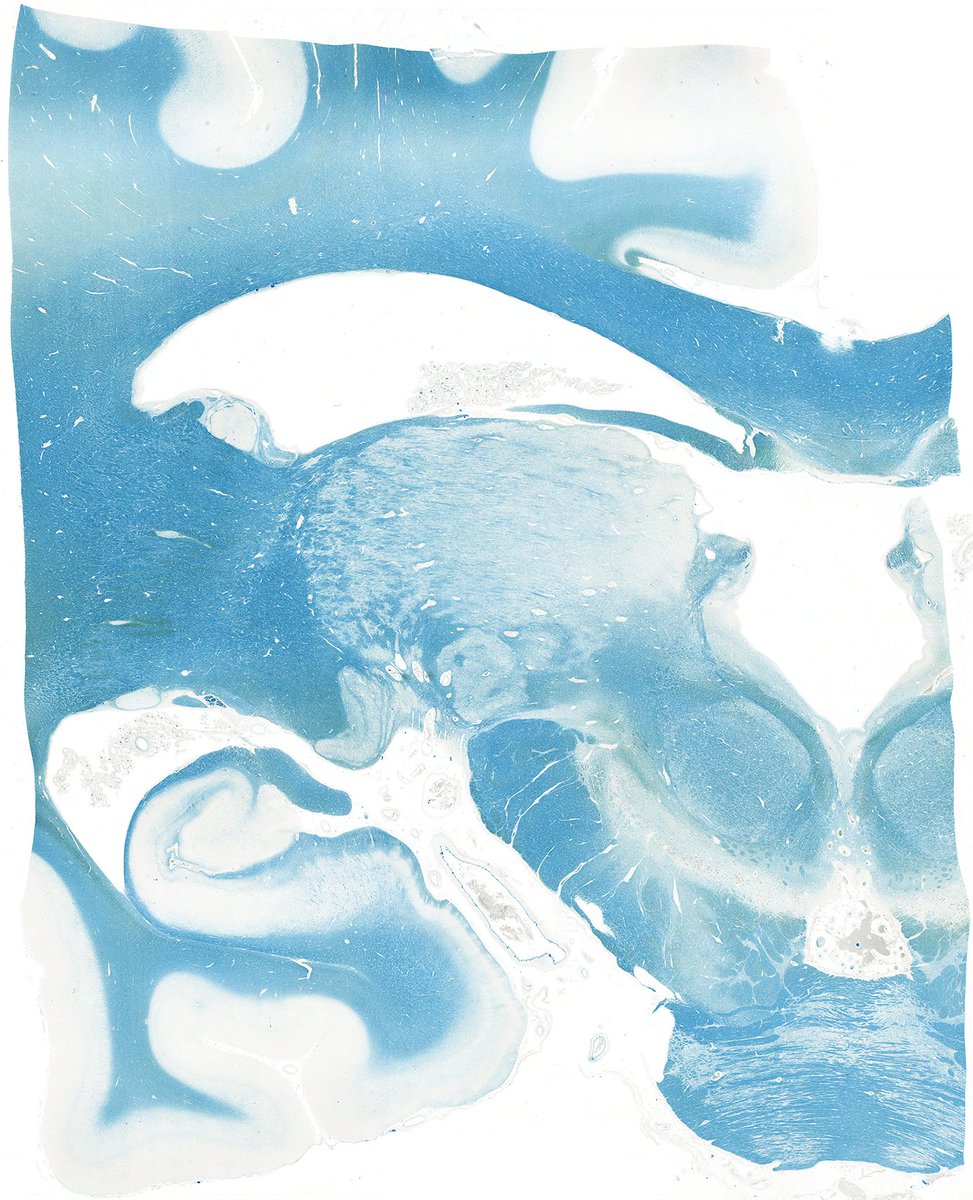

How many structures can you identify in this Luxol fast blue-stained section of

#brain?#neuropath#pathology#SoMe4pathologypic.twitter.com/P2iYb6zuxz